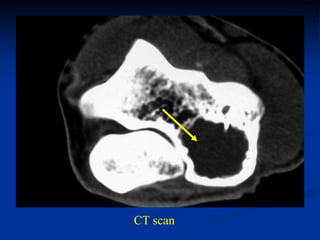

Case #609

30 year male

sessile based

osteochondroma

humerus

Coronal T-1 MRI

Coronal proton density MRI

cap

Axial T-1 MRI

fatty marrow

Axial T-2 MRI